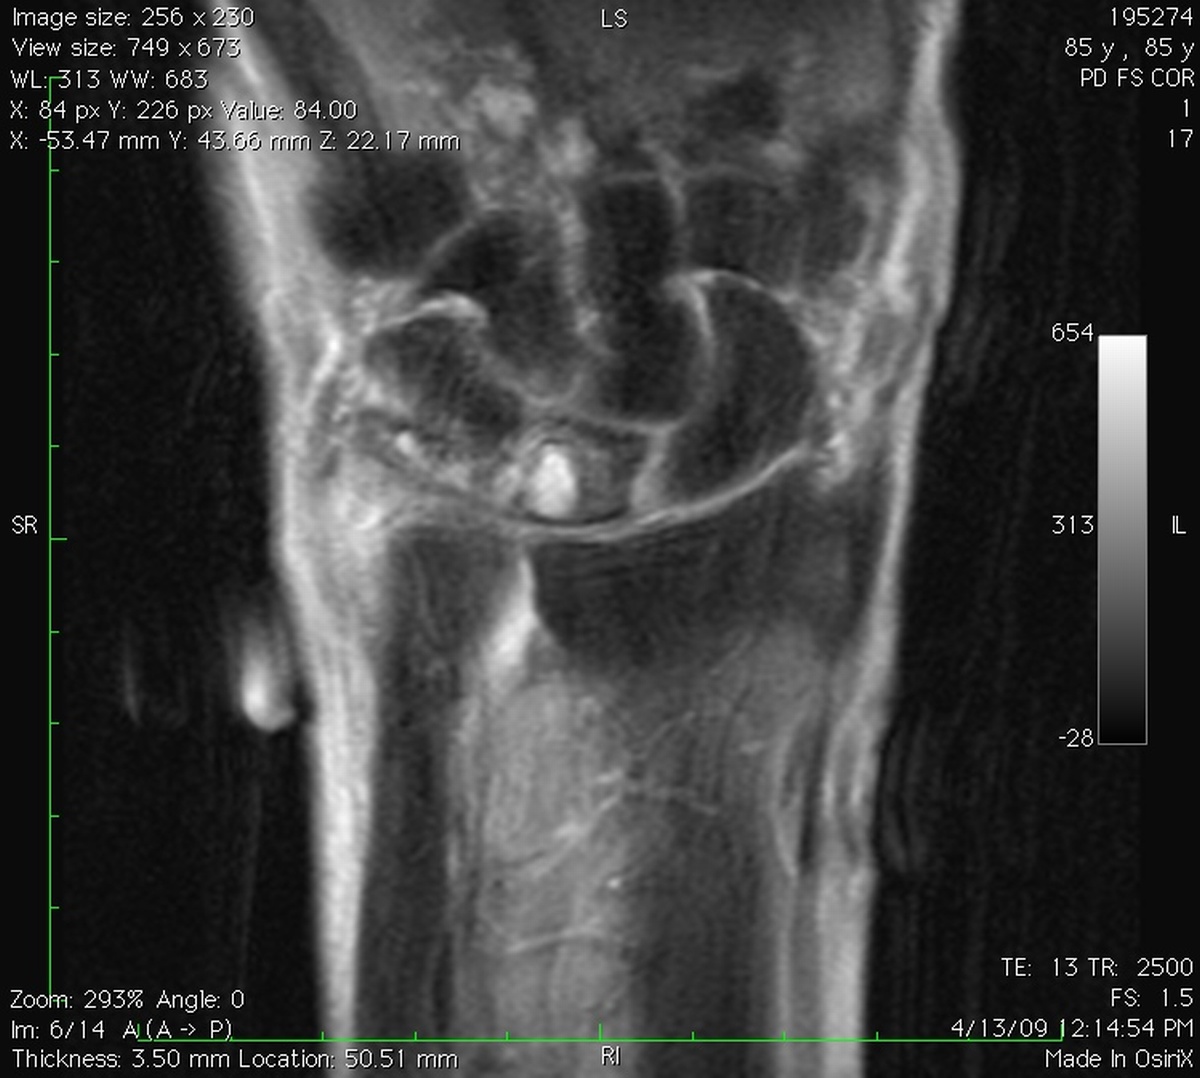

Clinical Example: Lunate Cyst

This imaging series was obtained for evaluation of a one month history of painful pronosupination in an active 85 year old man whose daily exercises include pushups.

lunate cyst